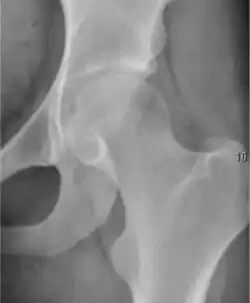

Plain radiography allows us to categorize the hip as normal or dysplastic or with impingement signs (pincer, cam, or a combination of both). Besides these, pathologic processes like osteoarthritis, inflammatory diseases, infection, or tumors can also be identified (Figure 1).[1]

Figure 1.

Osteoarthritis

In adults, one of the main indications for radiographs is the detection of osteoarthritic changes (Figure 1(e)). Nevertheless, radiographs usually detect advanced osteoarthritis that can be graded according to the Tönnis classifications. The grading system ranges from 0 to 3, where 0 shows no sign of osteoarthritis. Intermediate grade 1 shows mild sclerosis of the head and acetabulum, slight joint space narrowing, and marginal osteophyte lipping. Grade 2 presents with small cysts in the femoral head or acetabulum, moderate joint space narrowing, and moderate loss of sphericity of the femoral head. Grade 3 is the severest form of osteoarthritis, which manifests as severe narrowing of the joint space, large subchondral cyst with productive bone changes that may lead to deformity of the bone components of the joint, while secondary osteoarthritis due to calcium pyrophosphate deposition can be diagnosed when calcification of hyaline cartilage and fibrocartilage is detected.[1]

There are other pathological conditions that can affect the hip joint and radiographs help to make the appropriate diagnosis. Acute bacterial septic arthritis can be diagnosed by radiographs when a fast regional osteoporosis and destructive monoarticular process develops (Figure 1(f)). In case of tuberculous or brucella arthritis it is manifested as a slow progressive process, and diagnosis may be delayed.[1]